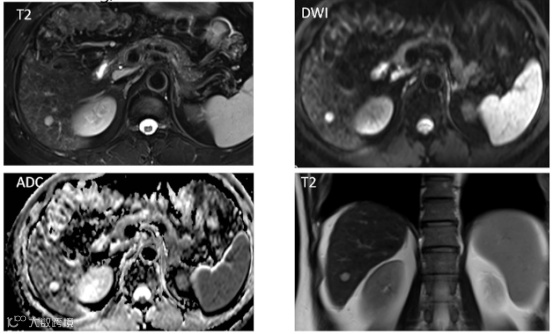

患者男,36岁,体检发现肝占位,临床及实验室检查无殊。

总结:T1低信号、T2高信号、DWI弥散信号、动脉期强化,但门脉期高信号,肝胆特异期瘢痕样低信号,不符合快进快出的表现,最终病理诊断为FNH。